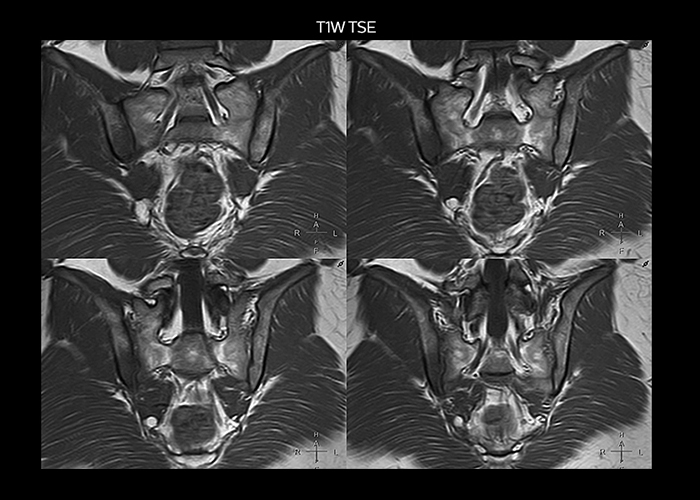

“To avoid coil changes we plan examinations of similar anatomies back to back, such as head and spine. Multiva helps us here a lot because coils don’t need to be changed frequently. Moreover, thanks to parallel imaging technology and 16-channel HeadSpineTorso and 8-channel MSK coils we are able to achieve excellent image quality. In this way Multiva helped us to increase both image quality and productivity.”

“Neurological cases, such as brain and spine imaging, represent the largest share in our MR scanning, followed by musculoskeletal cases. In general, we use simple and basic imaging protocols. But occasionally, we use advanced techniques for problematic cases if necessary.